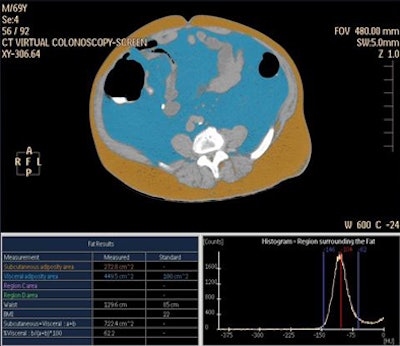

The researchers obtained semiautomated measurements of subcutaneous fat area (SFA), visceral fat area (VFA), and visceral fat percentage (VF% = 100 x VFA/[VFA+TFA]) at the umbilical level at noncontrast MDCT using a proprietary fat assessment tool (Philips Healthcare).

![]() |

| Histogram-based fat assessment software distinguishes abdominal visceral fat (blue) from subcutaneous fat (brown). |